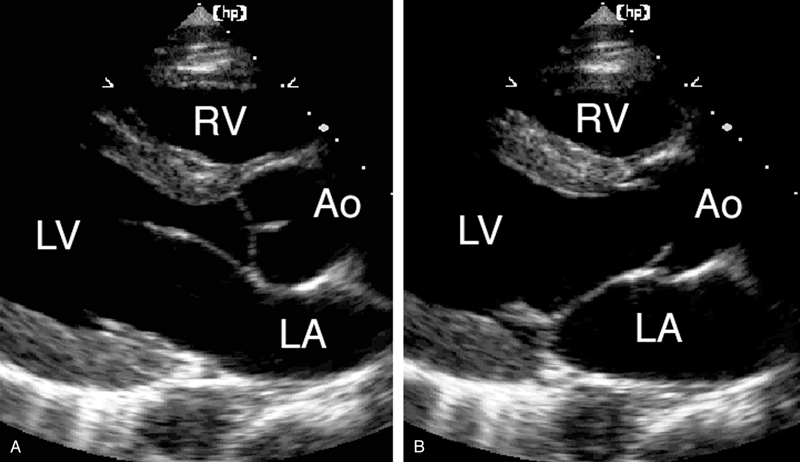

فحوصات تشخيصية لبعض امراض القلب والشرايين التاجية